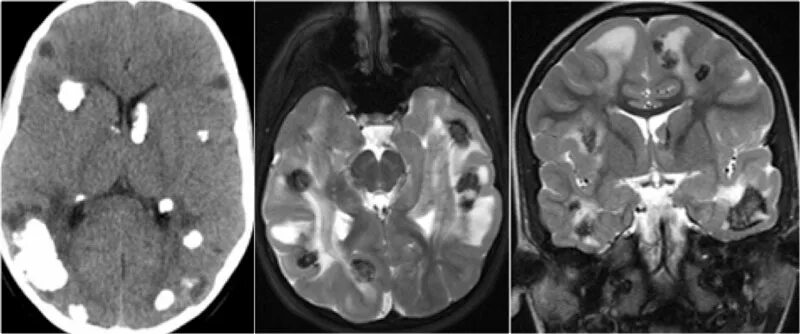

Туберкулезный склероз